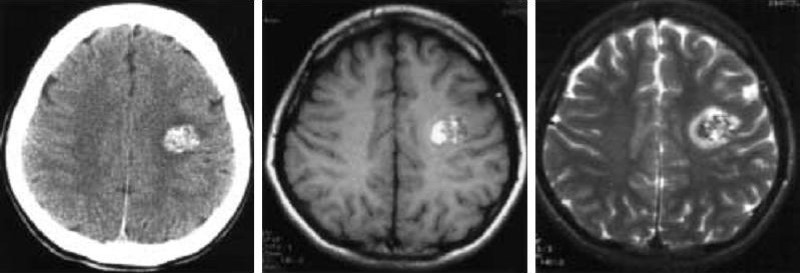

Hình 7 a/b/c. Calcified glioma hay u chảu máu? Bệnh nhân nữ 20 tuổi biểu hiện liệt mặt phải đột ngột. (Chẩn đoán mô bệnh học: cavernous angioma có chảy máu trong u).

a: chụp CT cho thấy một tổn thương tỷ trọng cao không đồng nhất với vùng giảm tỷ trọng bao quanh ở vùng dưới vỏ trung tâm bán cầu trái.

b và c: MRI. Cả hai ảnh SE T1-W (500/15) và FSE T2-W (3600/110) cho thấy sự trộn lẫn của nhiều nốt nhỏ cường độ cao và cường độ thấp trong tổn thương, đặc trưng của cavernous angioma. Phù bao quanh biểu hiện dưới dạng một vùng cường độ cao thay vì một viền cường độ thấp đặc trưng do chảy máu trong u (c).